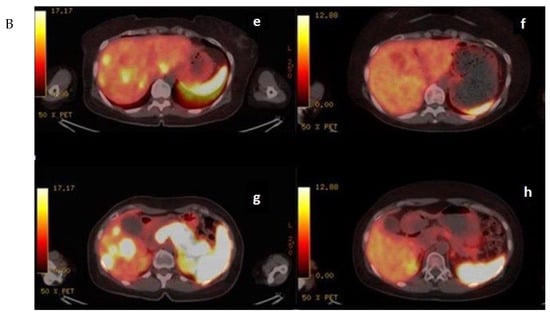

In the mTMZ + bevacizumab cohort of 30 patients, 4 (13.3%) exhibited a complete response (CR) (Figure 3), 15 (50.0%) demonstrated a partial response (PR), 7 (23.3%) had stable disease (SD), and 4 (13.3%) experienced progressive disease (PD). The overall objective response rate (ORR), combining CR and PR, reached 63.3% (19 patients), while the disease control rate (DCR), which includes CR, PR, and SD, stood at 86.7% (26 patients) (Table 2). In the course of our study evaluating the temozolomide–bevacizumab (mTMZ–bevacizumab) regimen for metastatic neuroendocrine tumors (NETs), treatment was continued until patients experienced intolerable side effects, disease progression, or death. Of the 30 patients included in our study, 18 patients reached mortality due to disease progression.

Figure 3.

(A) (upper) Downstaging tumors (complete response) after metronomic TMZ–bevacizumab combination therapy. MRI images for the patient with metastatic NET before (a,c) and six months after treatment (b,d); (B) (bottom) downstaging tumors (complete response) after metronomic TMZ–bevacizumab combination therapy. Gallium-68 (Ga-68)-DOTATATE positron emission tomography (PET) images for the patient with metastatic NET before (e,g) and one year after treatment (f,h).